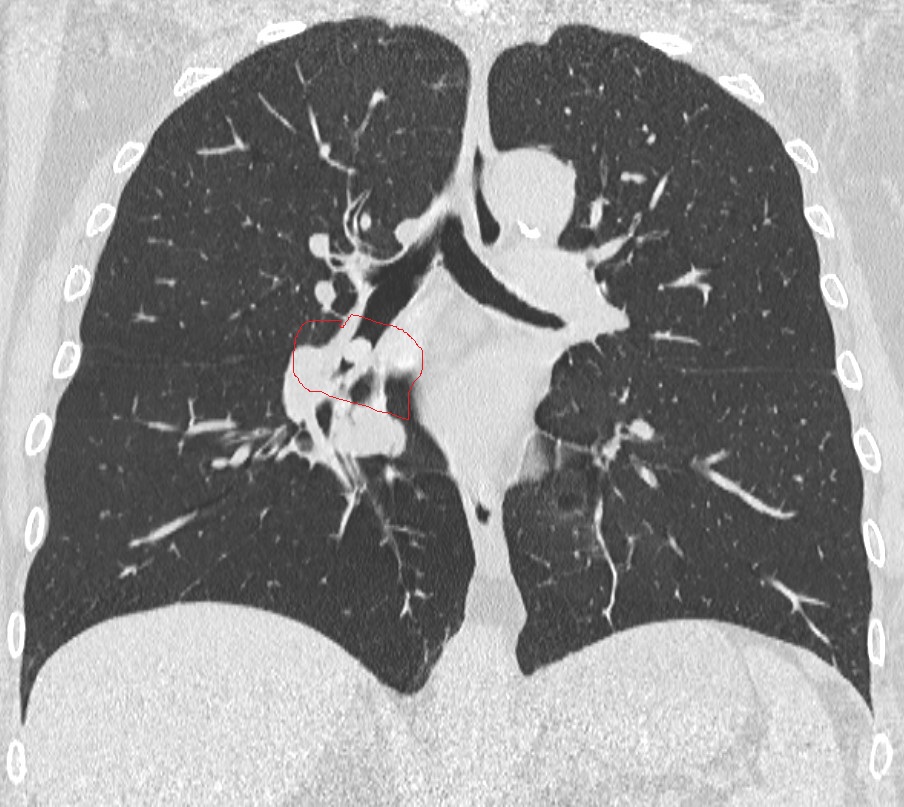

La paziente, giunta al pronto soccorso con forti difficoltà respiratorie e tosse persistente insorta durante il pranzo, è stata subito presa in carico dal personale medico dell’emergenza. Dopo gli accertamenti radiologici eseguiti dalla dottoressa Chiara Ragone, è emersa, tramite TAC toracica, una ostruzione subtotale del bronco inferiore del polmone destro, compatibile con la presenza di un corpo estraneo.

Trasferita d’urgenza in sala di Endoscopia Toracica, la donna è stata sottoposta a intervento in anestesia locale. Utilizzando un videobroncoscopio flessibile e una pinza a cestello, l’équipe guidata dal dottor Damiano Capaccio, con la collaborazione della dottoressa Alessandra Cotroneo, della capo sala Iolanda Cirillo e dell’infermiera Anna Zinna, è riuscita a rimuovere il corpo estraneo, risultato essere un seme di cece che si era accidentalmente incastrato nel bronco, causando un’occlusione quasi totale.